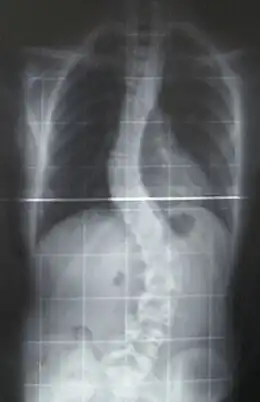

![]() Radiografía de una joven de 16 años y 8 meses con escoliosis vista de frente, de pie y con ropa (los pendientes y los aros del sostén son claramente visibles) | ||